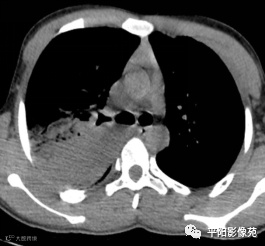

5天后复查X线片及CT:较前加重

影像特征:X线片右肺中上野片状高密度影,下缘以叶间裂为界,上缘及外侧缘模糊;CT位于右肺上叶后段,呈片状实变影,内见支气管影,边缘模糊。

影像诊断:右肺上叶大叶性肺炎。